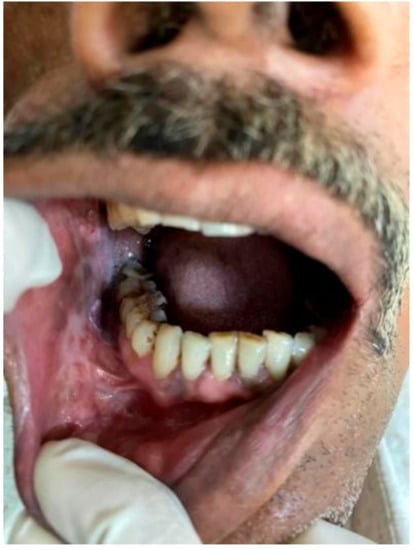

(a) Inclusion criteria for Group A: (Figure 1 and Figure 2)

Figure 1. Tobacco user’s lesion on left buccal mucosa leukoplakia.

Healthcare 10 01507 g001

Figure 2. Tobacco user’s lesion on right buccal mucosa along with oral submucous fibrosis.

Healthcare 10 01507 g002